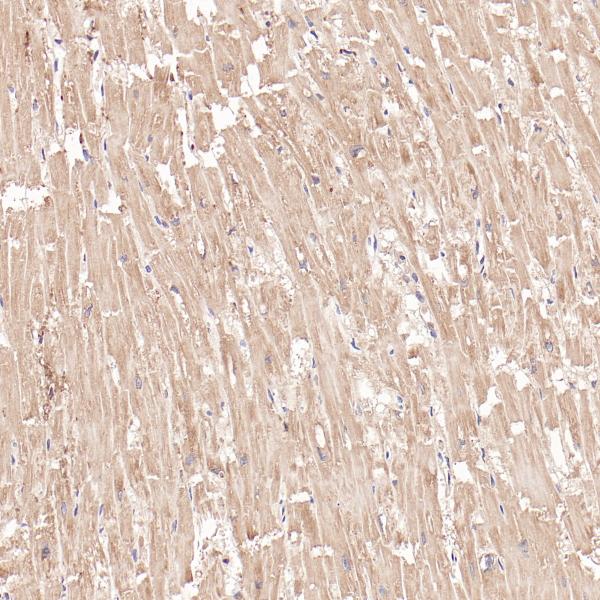

FABP3

BP6313

FOXL2

BP6235

FOXP1

BP6112

FOXP3

BP6166

FRα

BP6286